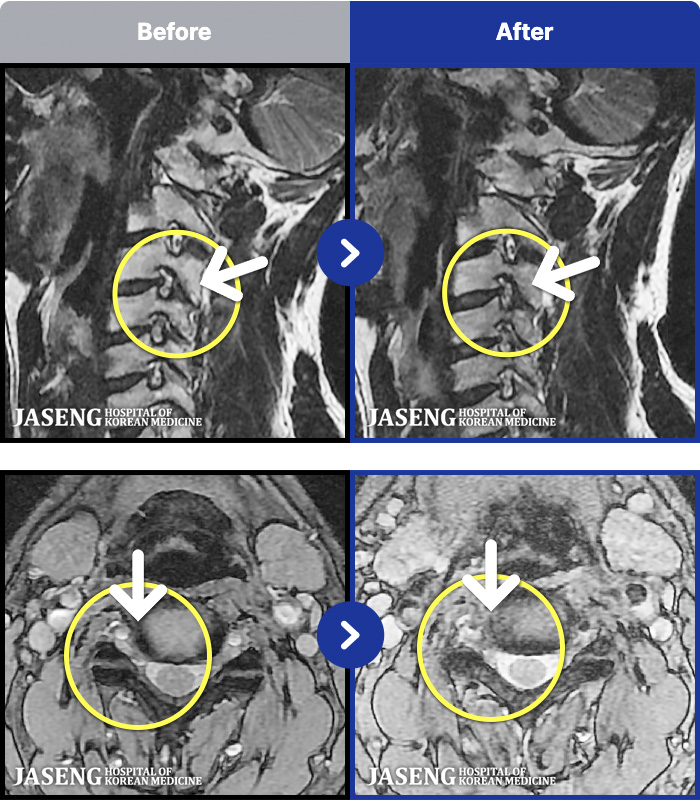

ȯںп Ǹ ǿ ԿǾ, ο ġ ۿ Ƿ ġḦ Ͻñ ٶϴ.